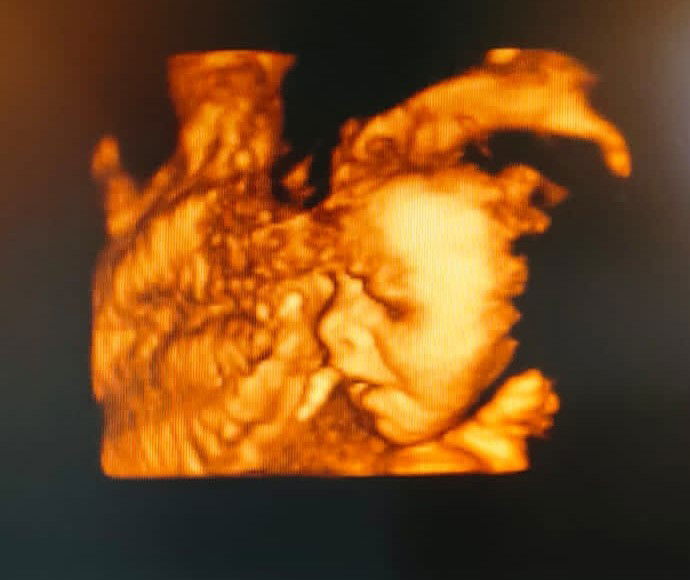

Setelah tahu positif aku periksa ke dokter kandungan. Dari hasil USG usia kandungan tujuh minggu, sudah terlihat kantung janin dan titik kecil banget, dokter minta untuk periksa dua minggu lagi. Deg-degan selama nunggu dua minggu. Dan Alhamdulillah dua minggu kemudian sudah ada detak jantung dan adik janin semakin besar, bukan lagi titik kecil.

Masuk bulan ke 5, aku mulai sering jalan pagi karna pusing sudah mulai tidak intens. Masuk bulan ke 6 pertumbuhan berat adik janin mulai pesat, begitupun dengan berat badanku. Di bulan ke 7 bertambah pesat lagi pertumbuhan adik janin.

Sekarang usia kandunganku tujuh bulan. Sudah mulai engap, perut seperti mau meletus, meskipun banyak yang bilang perut hamilku kecil. Sudah mulai tidak nyaman dengan posisi duduk, tidur, ataupun berdiri. Tapi begitulah kami berjuang bersama. Adik janin terus berjuang untuk tumbuh dan berkembang. Bulan depan dokter menyarankan untuk cek lab seperti cek darah. Semoga kami sehat selalu ya.